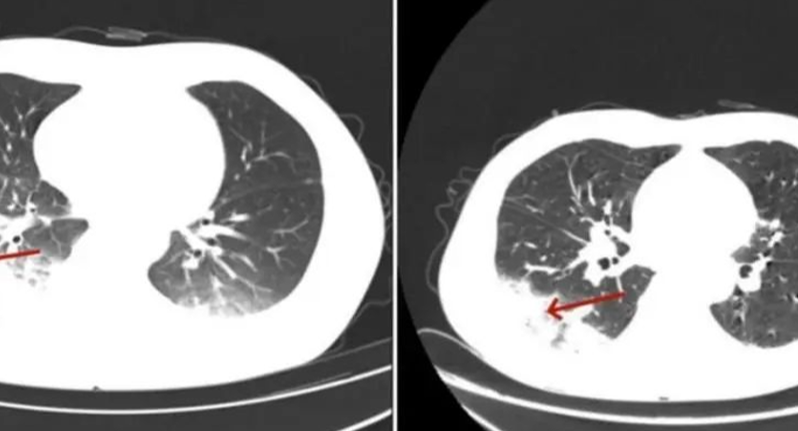

空调不洗干净,小心变成“白肺”

生活常识

军团菌

空调清洗